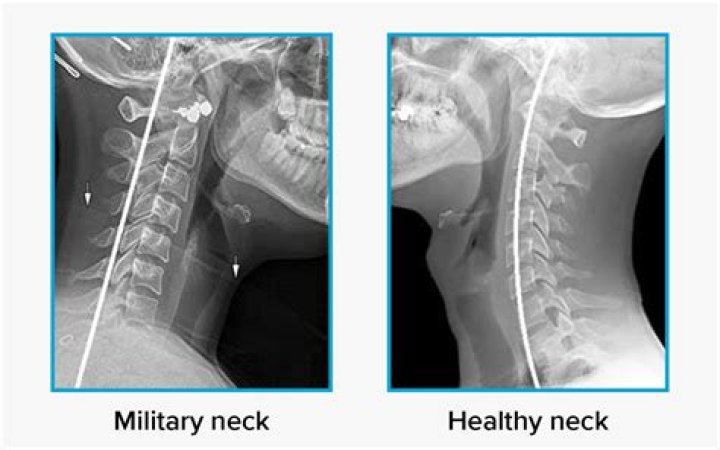

Military neck, or cervical kyphosis, is a rare condition that involves an abnormal curvature of the cervical spine, or neck. It can lead to severe disability and reduced quality of life. The natural curvature of the spine is important for maintaining posture and balance.

Military Neck (Cervical Kyphosis) is a disability that occurs when you lose flexibility in your neck and look like you’re stuck at attention. Military Neck is a disability that is more than a stiff neck. It is when a person, often a veteran, loses flexibility and looks like they are always standing at attention.

Is military neck rare?

Military neck is a rare disorder of the natural curvature of the spine that can cause severe disability in some people. People can develop military neck during childhood or adulthood.